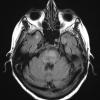

NEOPLASMS (HEMATOLYMPHOID)

Lymphoma, secondary (8)